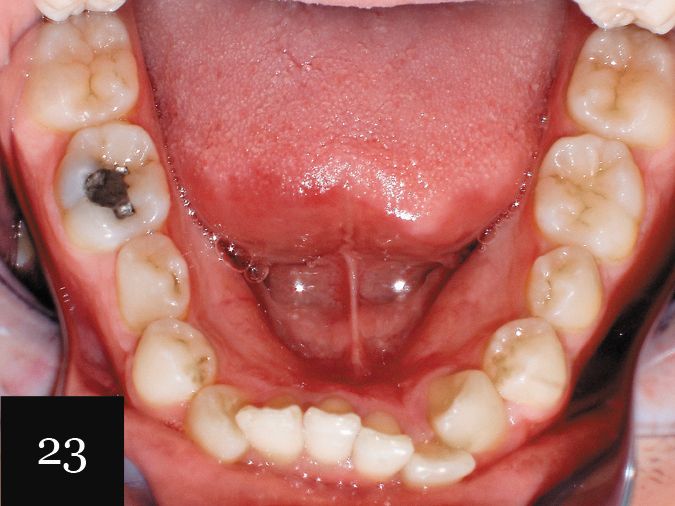

Again, these complex details were well captured using the Imprint 3 VPS impression material, and the patient was treated first with a series of 20 aligners, followed by a second impression and an additional 10 aligners. The hygiene issues were addressed as well, and the final result shows what we were able to achieve without resorting to periodontal surgery or grafting (Figs. 23 and 24).